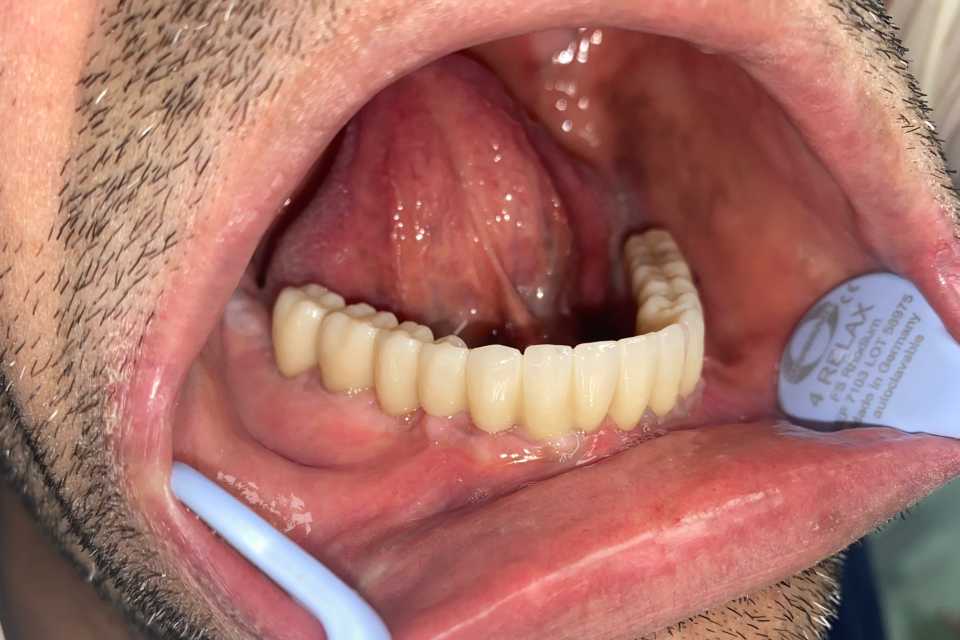

Pacientul Nicu D., în vârstă de 50 de ani, s-a prezentat în cabinet cu o edentație totală mandibulară în urma unei boli parodontale.

Împreună cu pacientul am hotărât realizarea unei lucrări protetice fixe inșurubabile pe 6 implanturi (implanturi Paltop). Lucrarea a fost realizată din ceramică pe zirconiu.

Implantul Paltop oferă posibilitatea realizării unor lucrări cu o estetică impecabilă și o afectare minimă a țesuturilor la locul implantării. Profilul concav al bontului protetic ajută la formarea unui țesut gingival dens la nivelul legăturii transgingivale scăzând vizibilitatea bontului.